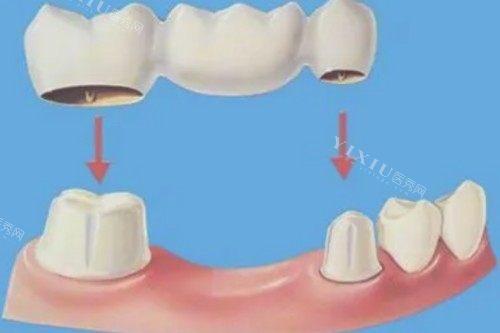

固定桥修复:牙科固定桥修复 4308 元起、搭桥固定桥 3721 元起、后牙双端固定桥 1285 元起、烤瓷固定桥 1566 元起、全瓷固定桥 1423 元起。